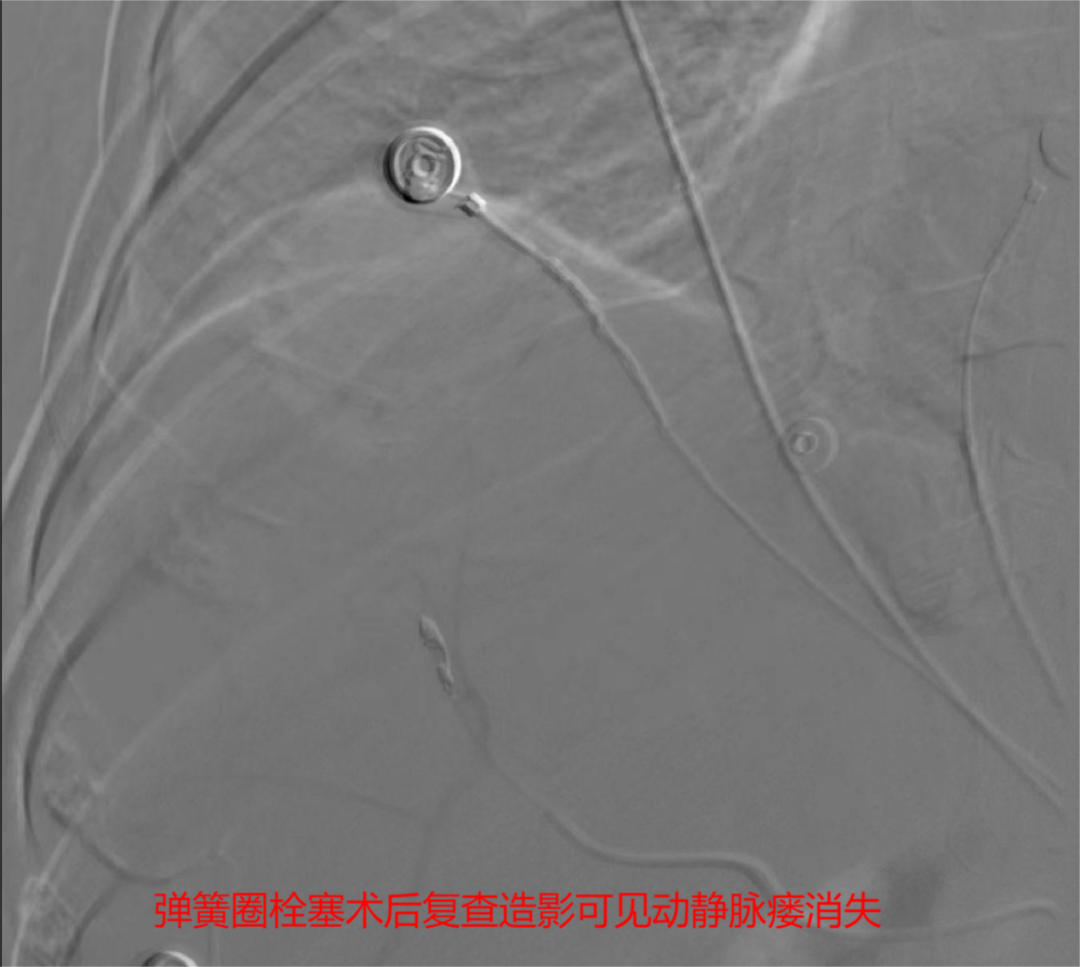

(2)动脉栓塞治疗:①肝损伤部位和拟栓塞的靶血管确定后,超选择性插入相关动脉主干近端,将明胶海绵根据需要剪成粗细不同的颗粒[直径1mmX(1~3mm)]或条块(lmm lmmX5mm),装入混有造影剂及庆大霉素的注射器内并摇匀,在透视监控下缓慢、少量、分次注入损伤血管,当血管血流明显缓慢或铸形,提示出血动脉已闭塞,再造影复查见造影剂外溢消失。

肝脏破裂介入治疗无需全麻,仅通过约1毫米的血管穿刺点进行血管内操作,在DSA下寻找出血点,用栓塞材料“堵”住止血点即可,可在短时间内达到快速止血、抢救病人生命的同时,大大减少血液制品的需求。这种新型的微创介入手术既可以及时抢救生命,又可以大大降低手术风险,减少并发症。时间就是生命,在征得患方同意后,介入团队迅速为患者实施手术抢救。近一个小时的手术,精准地将栓塞材料堵住出血点,成功挽救了患者的生命,提高了患者的生存质量,为患者的后续治疗赢得了机会。